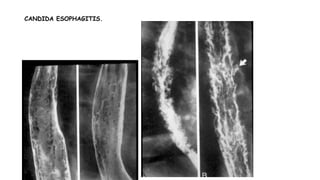

CANDIDA ESOPHAGITIS

• Radiographic findings include

1. Abnormql esophageal motility ( dilated, atonic esophagus ) is often an early stage

2. Irregular, nodular, plaque-like mucosal pattern ( arrow), irregular folds(arrowhead) with

marginal serrations ( shaggy appearance )

3. Multiple ulcerations of various sizes

4. Frequently involve the entire thoracic esophagus

CANDIDA ESOPHAGITIS.

• Shaggy esophagus associated with Candida infection , image "A" depicts the longitudinally oriented

plaque-like lesions visible in Candida esophagitis , image "B" depicts the granular appearance of

the esophageal mucosa secondary to edema and inflammation